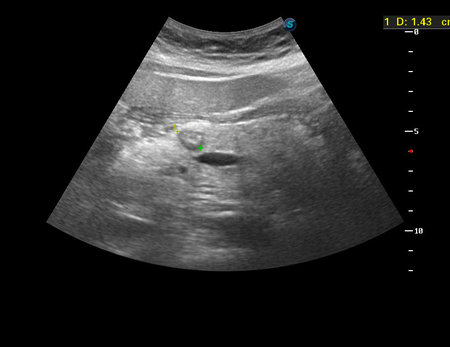

Женщина 68 лет, профилактическое исследование.

При исследовании в ПЖ обнаружено очаговое образование с достаточно ровными контурами.

КТ: эндокринное новообразование, инсулома?

Выполнена резекция тела панкреас.

Гистология: нейроэндокринная опухоль G1